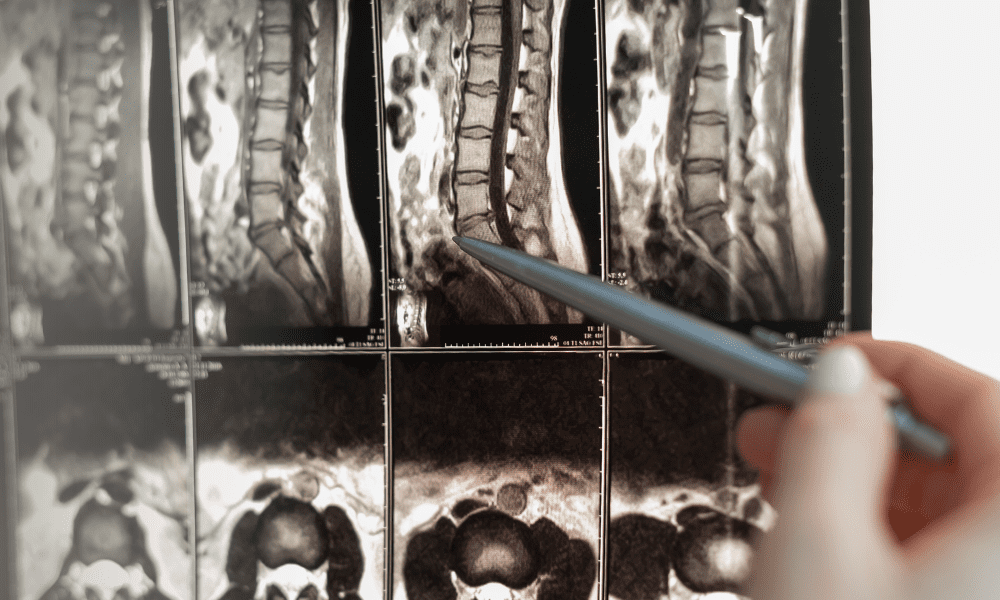

A common manifestation of DDD is its association with sciatica, a condition characterized by pain that radiates along the sciatic nerve. The question, “Does degenerative disc disease cause sciatica?” is frequently posed by patients experiencing this debilitating symptom.

The answer lies in the intricate anatomy of the spine, where degenerated discs may impinge on nerve roots, giving rise to the dual challenge of degenerative disc disease and sciatica.